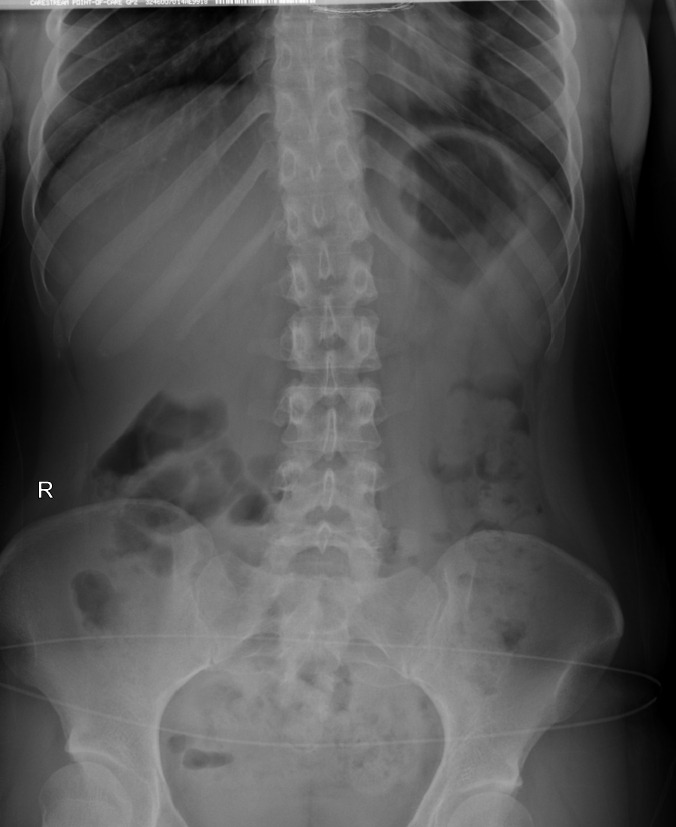

우측 경골이 2.5cm 더  길다. 그 결과로 골반, 척추의 측만증이 발생함.

3. 천골이 nutation, 틀어짐.

요추가 좌측회전, 측만발생

4. 요추 과전만, sacral angle증가